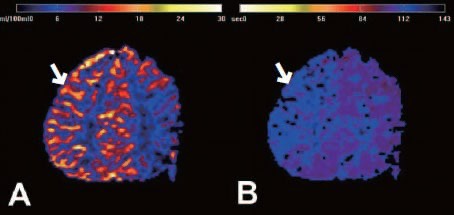

모야모야병은 현재 의학적으로 완치가 불가능한 질환으로 분류됩니다. 이미 좁아진 혈관을 다시 정상화시키는 방법은 없기 때문입니다. 그러나 “완치 불가”라는 표현은 절망이 아니라, 아래와 같은 관리 체계를 의미합니다.

① 수술을 통해 새로운 혈류 경로를 충분히 확보하면, 뇌졸중 위험을 크게 줄이고 거의 정상적인 생활을 유지할 수 있습니다.

② 조기 진단 후 적절한 치료를 받은 환자는 장기적으로 매우 안정적인 경과를 보일 수 있습니다.

③ 꾸준한 추적 검사와 생활 관리로 발작 감소·인지기능 유지·일상 회복이 충분히 가능합니다.

즉, 완전한 치유는 어렵지만 “충분히 관리 가능한 만성 질환”이며, 대부분의 환자가 수술 후 학교·직장·일상생활로 정상 복귀하고 있습니다.